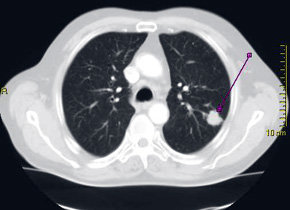

Nódulos pulmonares e detectan en forma accidental

Muchas veces los nódulos pulmonares se detectan en forma accidental, a través de exámenes como una radiografía o scanner de tórax que se solicitó por otros motivos.

El jefe del servicio de Neumología Intervencional de Clínica Alemana, doctor Sebastián Fernández-Bussy, explica que este nuevo método, conocido como Lungpoint, permite hacer una reconstrucción virtual del pulmón, mediante un software que utiliza el scanner de tórax del paciente para marcar el nódulo que se quiere biopsiar. Luego, ese mismo programa realiza una especie de navegación virtual hacia la lesión, indicando qué camino tomar para llegar a través de una broncospía (procedimiento mínimamente invasivo) al nódulo y hacer la biopsia, “es como un GPS pulmonar”, afirma.

La nueva técnica se utiliza en nódulos pulmonares que miden más de 15 milímetros.”Tradicionalmente, en la mayoría de las lesiones de este tipo, es necesario realizar una cirugía para tomar la biopsia, sin embargo, con esta nueva técnica se ofrece una alternativa diagnóstica menos invasiva”, explica el especialista.